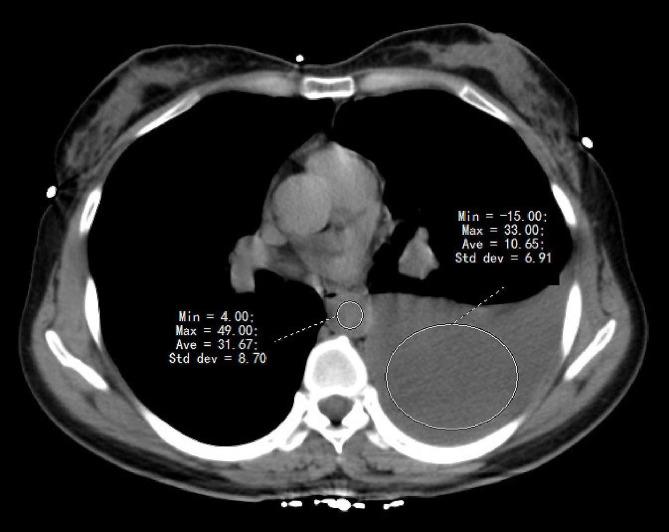

Computed tomography (CT) scan is commonly performed for pleural effusion diagnostis in the clinic. However, there are limited data assessing the accuracy of thoracic CT for the separation of transudative from exudative effusions. The study aimed to determine the diagnostic value of thoracic CT in distinguishing transudates from exudates in patients with pleural effusion.

This is a two-center retrospective analysis of patients with pleural effusion, a total of 209 patients were included from The First Affiliated Hospital of Henan University of Science and Technology as the derivation cohort (Luoyang cohort), and 195 patients from the First Affiliated Hospital of Zhengzhou University as the validation cohort (Zhengzhou cohort). Patients who underwent thoracic CT scan followed by diagnostic thoracentesis were enrolled. The optimal cut-points of CT value in pleural fluid (PF) and PF to blood CT value ratio for predicting a transudative vs. exudative pleural effusions were determined in the derivation cohort and further verified in the validation cohort.

In the Derivation (Luoyang) cohort, patients with exudates had significantly higher CT value [13.01 (10.01-16.11) vs. 4.89 (2.31-9.83) HU] and PF to blood CT value ratio [0.37 (0.27-0.53) vs. 0.16 (0.07-0.26)] than those with transudates. With a cut-off value of 10.81 HU, the area under the curve (AUC), sensitivity, specificity, positive predictive value (PPV) and negative predictive value (NPV) of CT value were 0.85, 88.89%, 68.90%, 43.96%, and 95.76%, respectively. The optimum cut-value for PF to blood CT value ratio was 0.27 with AUC of 0.86, yielding a sensitivity of 61.11%, specificity of 86.36%, PPV of 78.57%, and NPV of 73.08%. These were further verified in the Validation (Zhengzhou) cohort.

CT value and PF to blood CT value ratio showed good differential abilities in predicting transudates from exudates, which may help to avoid unnecessary thoracentesis.